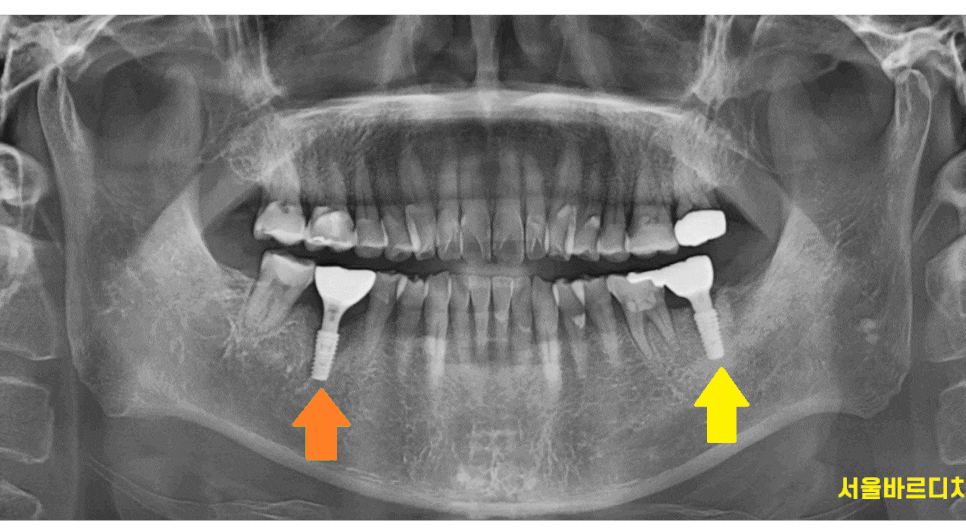

230214

아프지는 않다고 하셨지만

오른쪽 아래 어금니 치아도 염증이 있었습니다.

231029

이미 잇몸 밖으로 여드름 마냥

고름이 나오고 있었거든요ㅠㅠ

아픈 왼쪽 아래 부위는

발치한 당일에 하남 미사 치과에서

임플란트를 심어 드렸습니다.

230926

240329